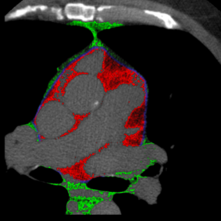

The quantification of fat depots on the surroundings of the heart is an accurate procedure for evaluating health risk factors correlated with several diseases. However, this type of evaluation is not widely employed in clinical practice due to the required human workload. This work proposes a novel technique for the automatic segmentation of cardiac fat pads. The technique is based on applying classification algorithms to the segmentation of cardiac CT images. Furthermore, we extensively evaluate the performance of several algorithms on this task and discuss which provided better predictive models. Experimental results have shown that the mean accuracy for the classification of epicardial and mediastinal fats has been 98.4% with a mean true positive rate of 96.2%. On average, the Dice similarity index, regarding the segmented patients and the ground truth, was equal to 96.8%. Therfore, our technique has achieved the most accurate results for the automatic segmentation of cardiac fats, to date.

翻译:心脏周围脂肪库的量化是评价与若干疾病相关的健康风险因素的准确程序。然而,由于需要人的工作量,这种评价在临床实践中没有被广泛采用。这项工作提出了心脏脂肪垫的自动分解新技术。该技术的基础是对心脏CT图像的分解应用分类算法。此外,我们广泛评价了这项任务的若干算法的性能,并讨论了这些算法提供了更好的预测模型。实验结果显示,震动和中间脂肪分类的平均准确性为98.4%,平均真实正率为96.2%。平均而言,关于分解病人和地面真相的骰子相似性指数为96.8%。我们的技术迄今为止在心脏脂肪的自动分解方面已经取得了最准确的结果。